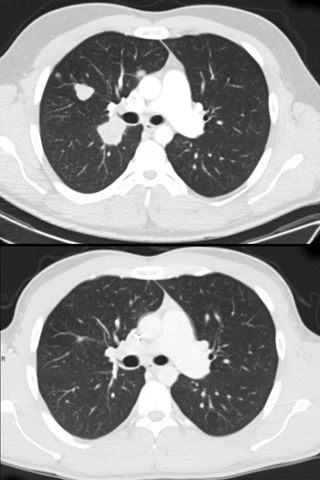

Spencer Laird's medical scansCredit: Duke Health

Spencer Laird's medical scans

After this scan, Spencer found out that not only had his cancer returned, but it had spread to his lungs. He had 13 tumors, and one was the size of a golf ball, according to the outlet. Because of this, Spencer's doctor estimated he only had about two years to live.

"I stayed up days and just stared at his scans," CarleyAnn added. "This was strictly me not wanting to lose my husband and having to tell my 5-year-old."